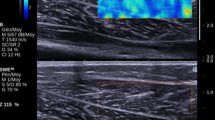

All participants received a USWE examination from experienced physical therapists (P.W.Y. and Z.J.P.) with 4 years of experience performing ultrasonography. In addition, the USWE examination was supervised by a sonographer (S.T.X.X) with 13 years of experience. The shear modulus was quantified with an AixPlorer ultrasonic scanner positioned on the skin markers in the neutral position and relaxed position of the ankle joint. To ensure that the muscle and tendon regained their original elastic properties and to relieve the tension on the GDF between angle switching, the shear modulus at each joint angle was measured at 5-min intervals22. First, as described in our previous studies23,24,25, we applied sufficient ultrasound gel to the skin markers. Second, the midpoint of the transducer was placed in the markers, and the B-mode was activated to ensure that the muscle belly was assessed and then rotated in a longitudinal orientation until the grayscale image displayed the appearance of the muscle (Fig. 1). Third, the mode of USWE was activated, the transducer was kept motionless for more than 8 s, and the image was frozen until the color in the ROI was uniform and several fibers were continuously visible16,17,19,20. Three images were captured at each measurement site of muscle fascia. Image quality was closely monitored throughout all measures.

Typical maps of the elastic properties of the MGF and LGF in the longitudinal directions. Color-coded boxes representing muscle fascia elasticity are shown in the upper images. The longitudinal grayscale sonograms of muscle fascia are shown in the bottom images. The measurement of shear modulus is performed in a circle. The Q-Box™ is shown on the right. MGF: medial gastrocnemius fascia; LGF (B): lateral gastrocnemius fascia.